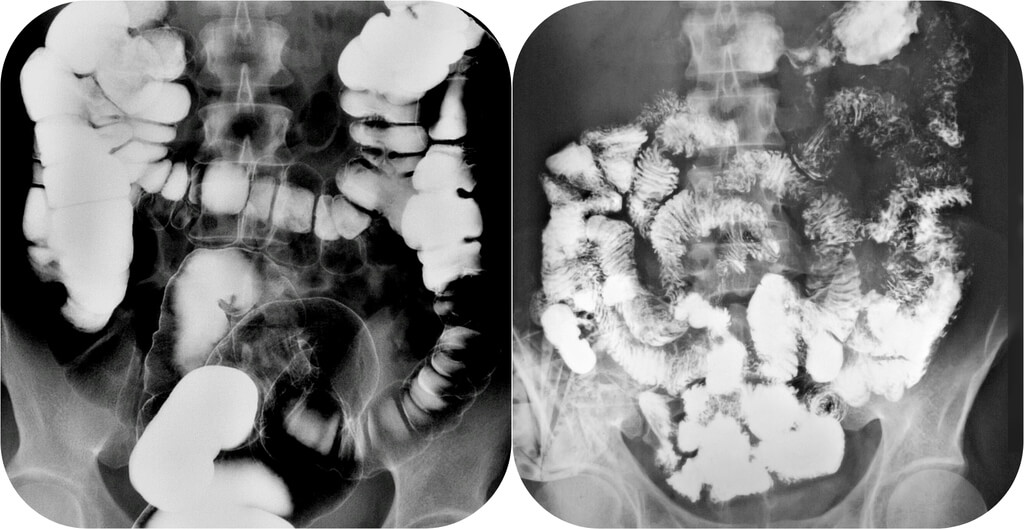

Рентгенография небного шва: Медицинские исследования и диагностика